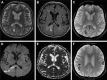

Background: Secondary central nervous system lymphoma (SCNSL) is a rare and aggressive disease, which is defined as secondary central nervous system (CNS) involvement in patients with systemic lymphoma. According to previous reports, SCNSL presents mostly with leptomeningeal spread; however, our experience differs. In the present study, we demonstrate the diversity of magnetic resonance imaging (MRI) patterns in SCNSL.

Patients and methods: Initial morphological MRI findings in 21 patients (10 women and 11 men with mean age 62.3±16.2 years) with SCNSL were retrospectively evaluated. All patients suffered from neurological symptoms and underwent MRI, and all cases were histologically verified. Twelve patients were treated by corticosteroids at the time of the initial MRI.

Results: Parenchymal lesions were present in 18 of 21 cases (85.7%), solitary meningeal infiltration was present in 1 patient (4.8%), leptomeningeal infiltration in combination with hypophyseal involvement in 1 patient (4.8%), and solitary involvement of the sixth cranial nerve (CN) was found in 1 patient (4.8%). Multiple lesions were present in 11 of 21 cases (52.4%). Diffusion restriction in all or part of the lesion was detected in 14 of 18 cases (77.8%). All parenchymal lesions had an infiltrative appearance and most enhanced homogenously (11 of 17 cases; 64.7%). A combination of parenchymal and meningeal involvement was found in 10 of 21 cases (47.6%). Infiltration of the CNs, basal ganglia, corpus callosum, and ependyma was present in 8 of 21 cases (38.1%) for each of the abovementioned structures; hypothalamic-hypophyseal axis was affected in 7 of 21 cases (33.3%).

Conclusion: In contrast to previous reports, SCNSL presented as parenchymal disease. MRI is not sufficient for differentiation between primary and secondary CNS lymphoma.